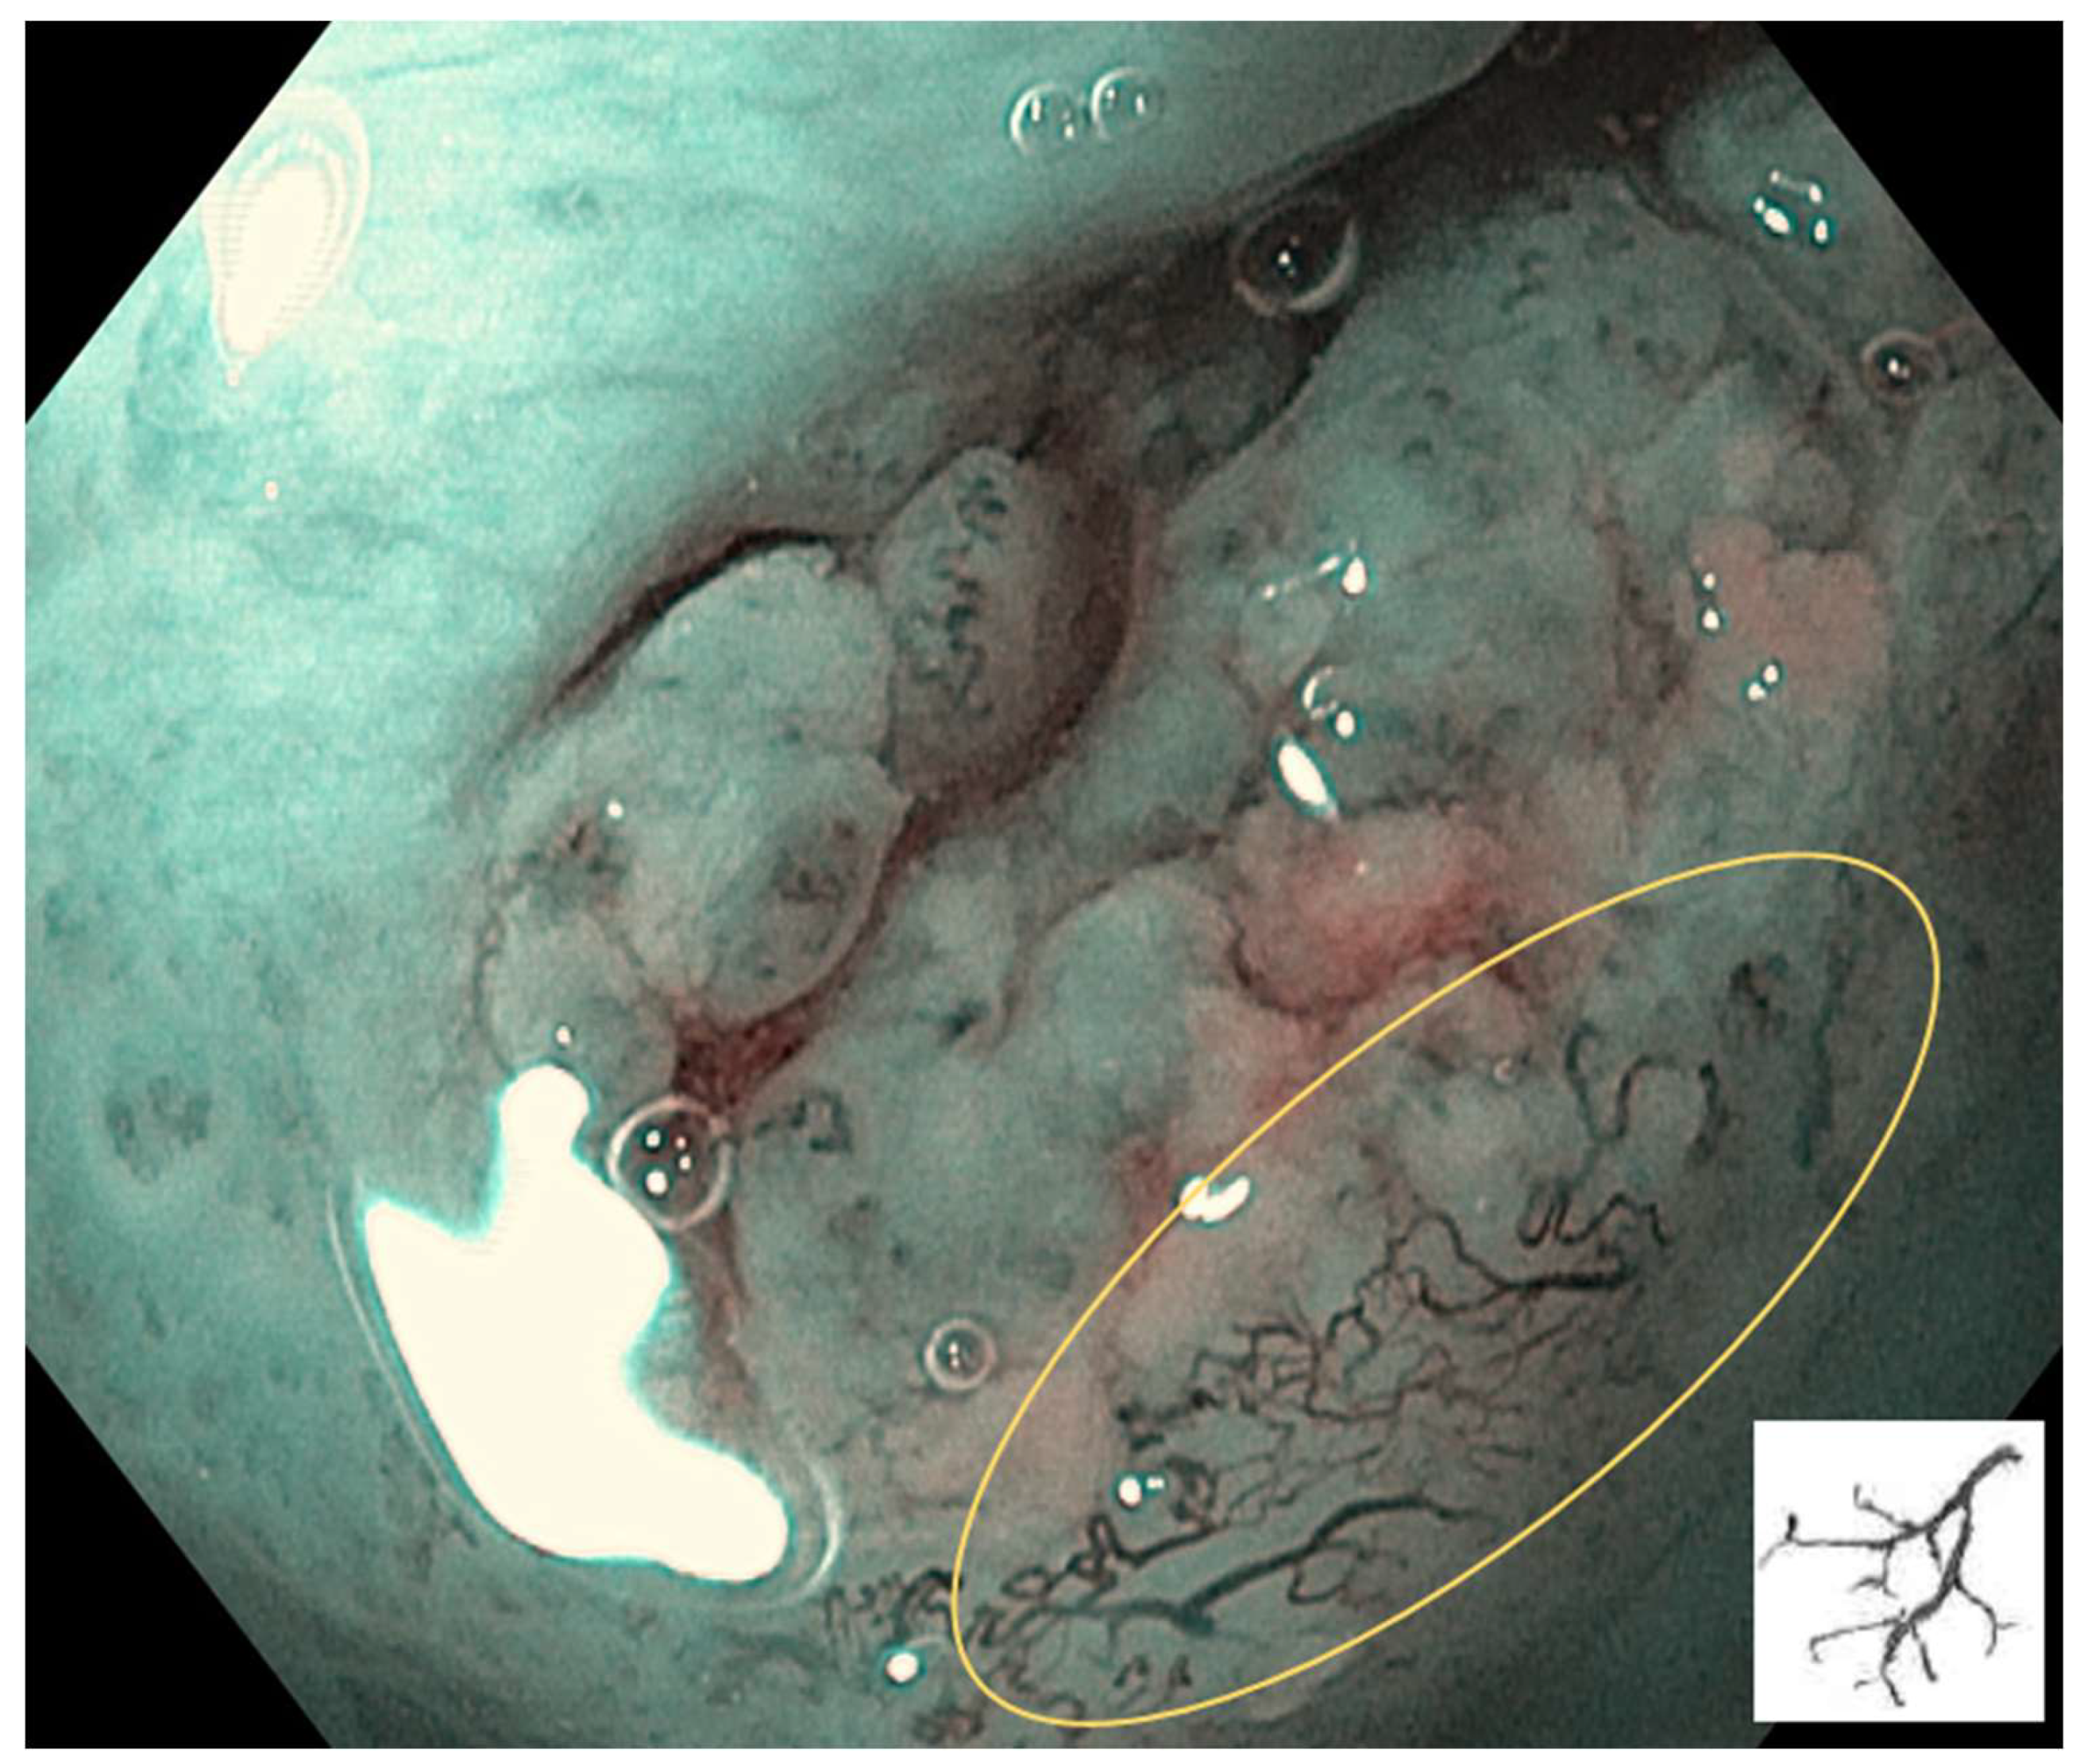

Type III: IPCL is further elongation and meandering. Mainly seen in neoplastic lesions (Figure 4).

Figure 4. Type III: IPCL is further elongation and meandering. Mainly seen in neoplastic lesions.